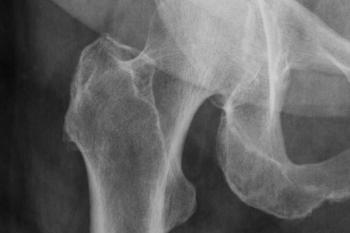

An analysis of data from more than 65k patients suggests low-dose CT scans could provide an opportunity to screen for osteoporosis in older patients.